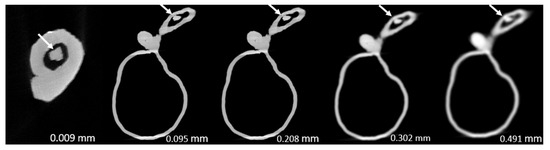

- Model 3: >90% and 70% stenosis in proximal LCx and middle LCx, respectively.

| 3 | 94.4 ± 0.000 | 99.2 ± 0.005 | 97.2 ± 0.009 | 97.8 ± 0.005 | 100 ± 0.000 | <0.0005 |

| 3 | 75.0 ± 0.000 | 71.5 ± 0.011 | 75.2 ± 0.017 | 74.7 ± 0.021 | 85.1 ± 0.078 | 0.091 |